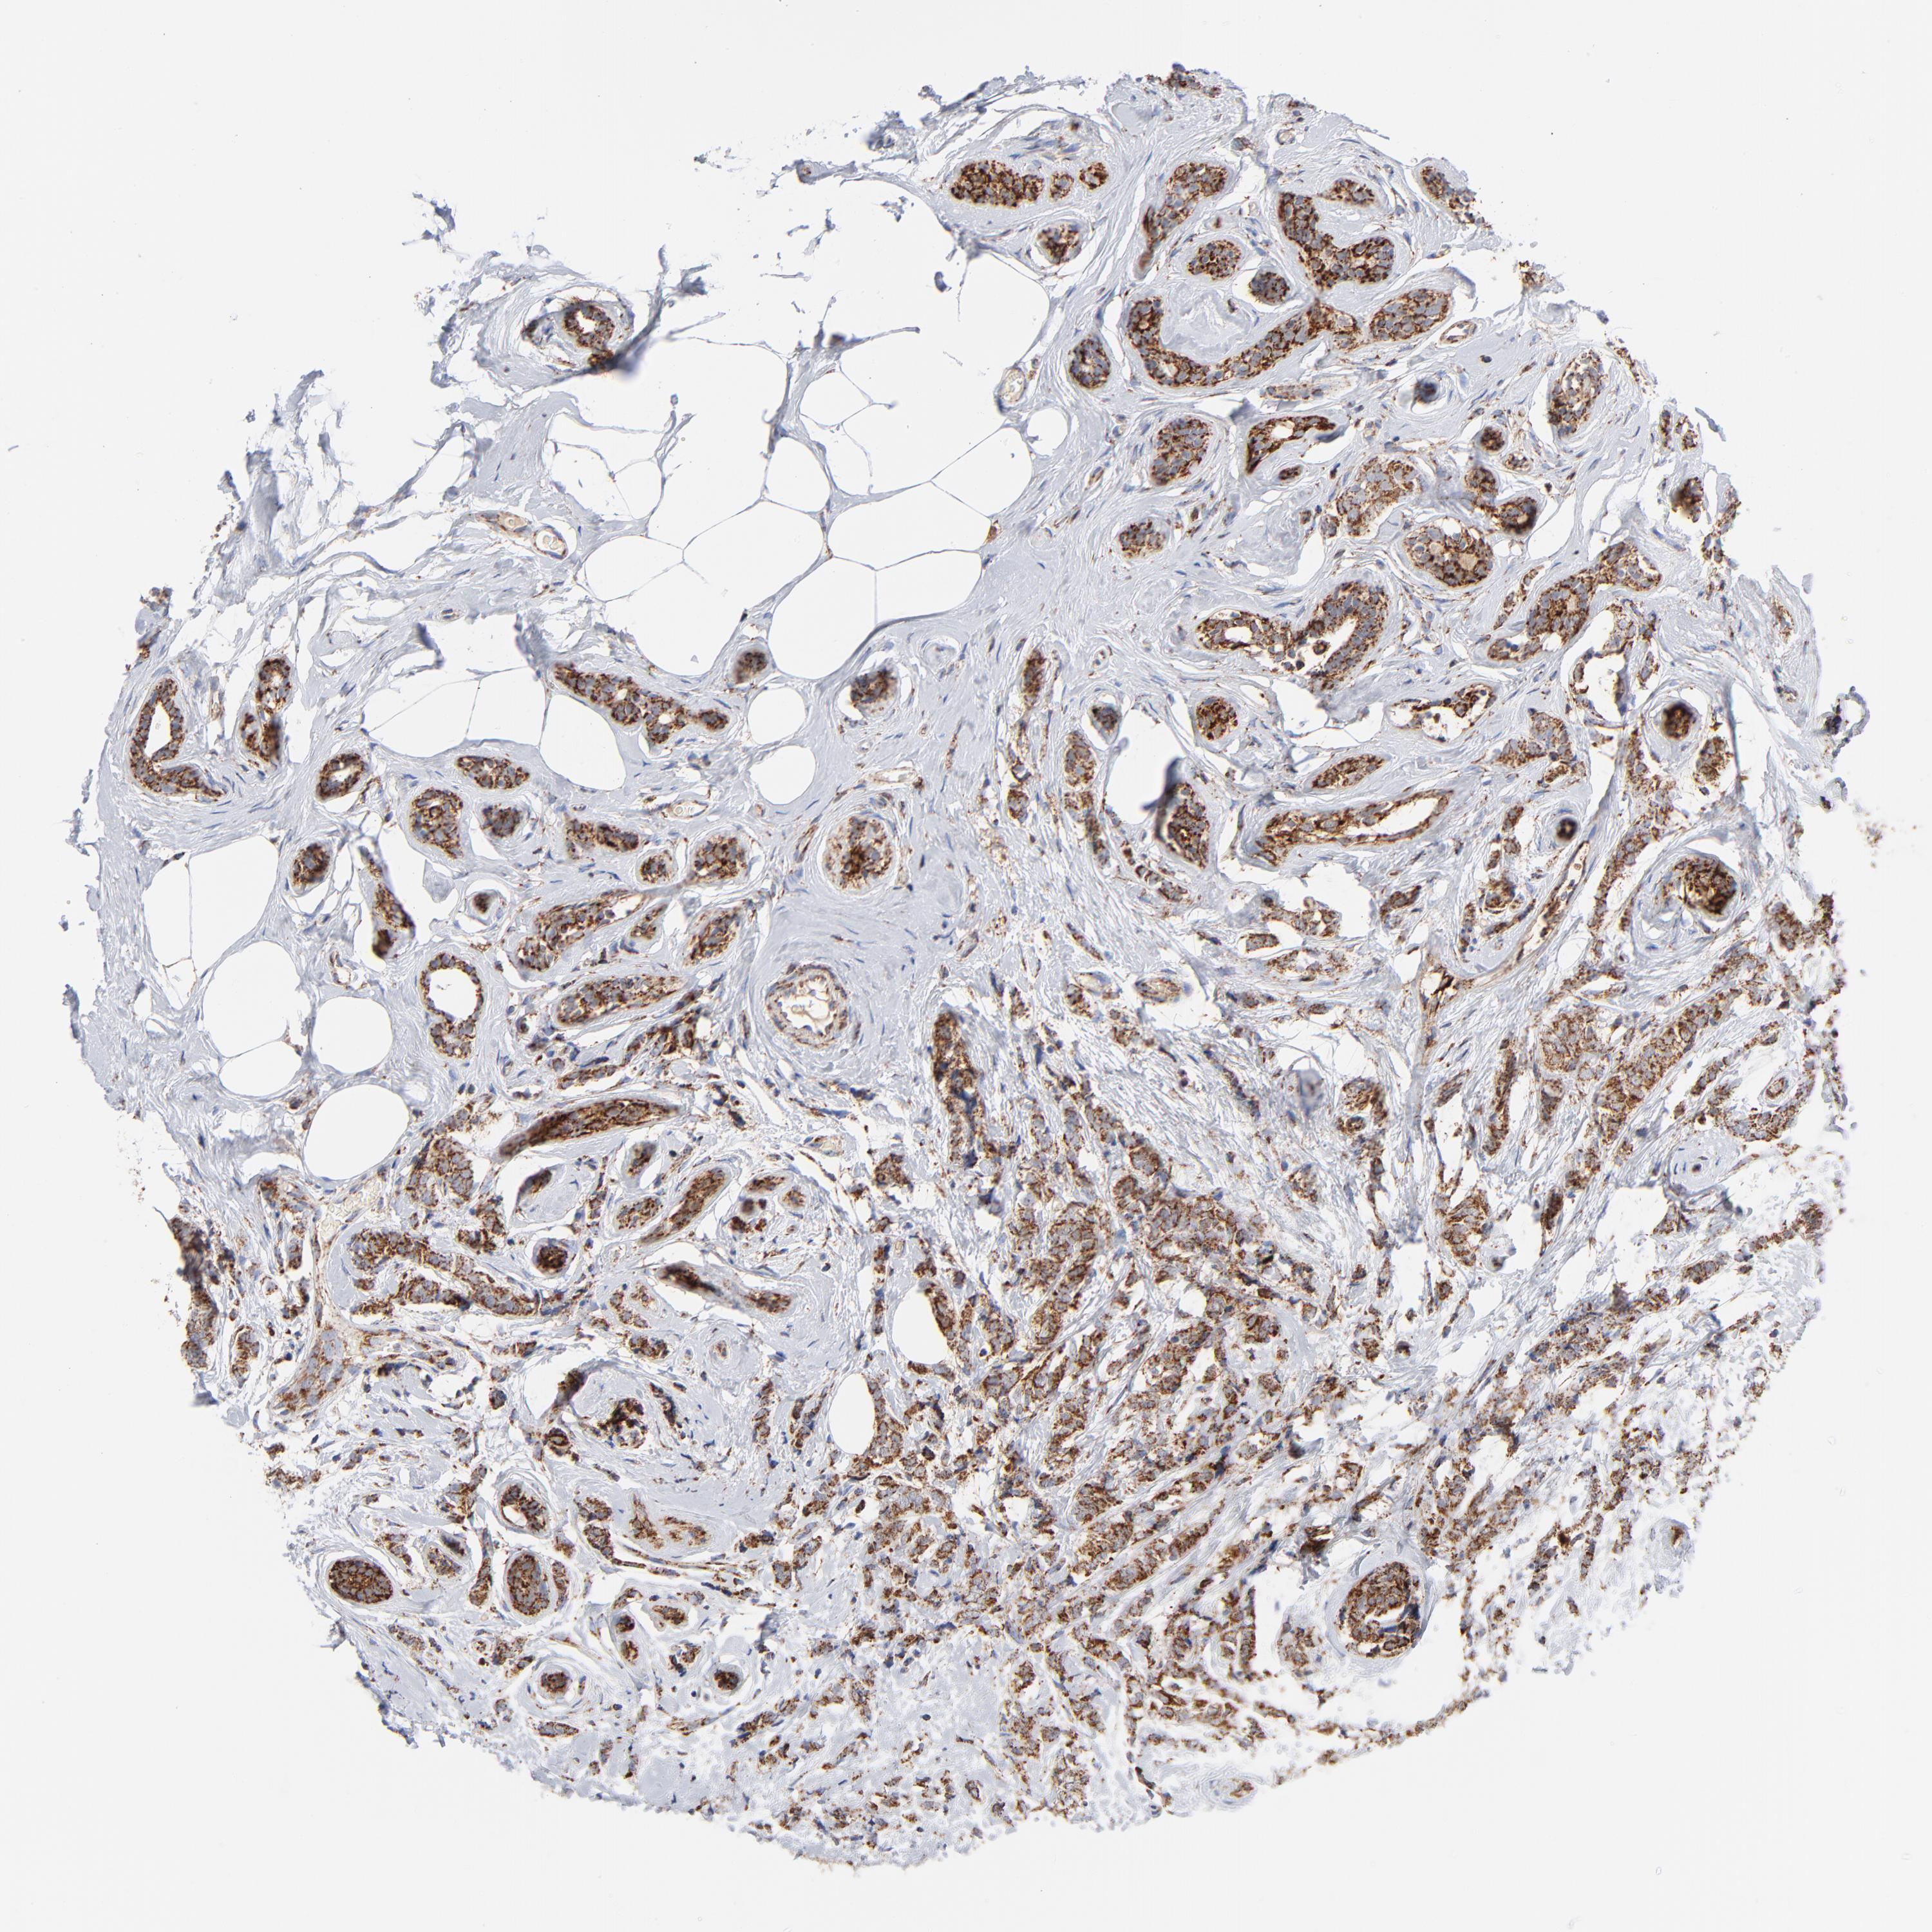

CANCER BREAST CANCER Show tissue menu

BRCA TCGA BRCA VALIDATION PROTEIN EXPRESSION